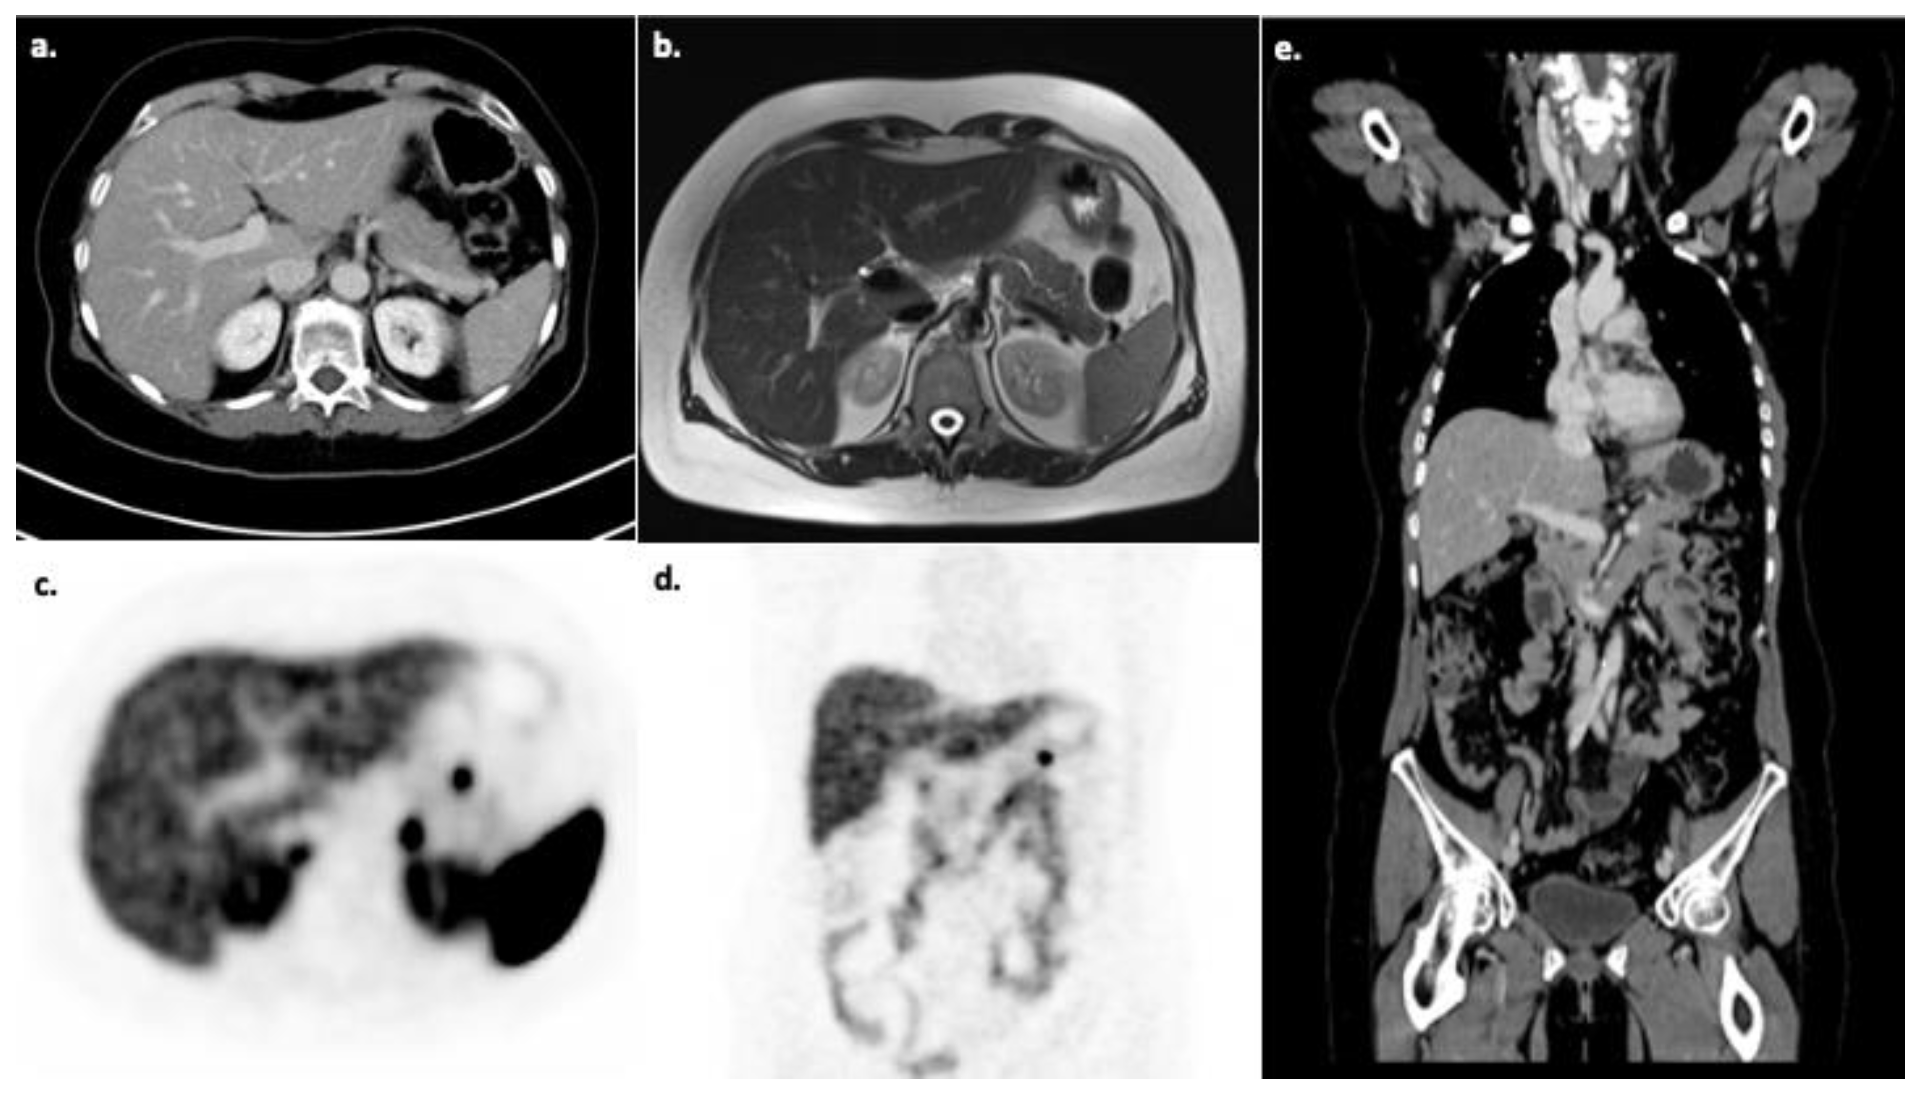

- Tolomeo, A.; Lopopolo, G.; Dimiccoli, V.; Perioli, L.; Modoni, S.; Scilimati, A. Impact of 68Ga-DOTATOC PET/CT in comparison to 111In-Octreotide SPECT/CT in management of neuro-endocrine tumors: A case report. Medicine 2020, 99, e19162. [Google Scholar] [CrossRef] [PubMed]